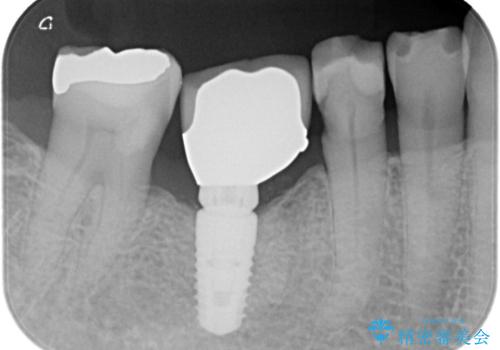

- 虫歯が原因で歯が欠けていました。昔詰めた保険の材料(CR)が劣化しその下が虫歯になっている状態でした。

色々な箇所にCR(保険の材料)を詰めてあったので、CRと虫歯を全部除去した後、オールセラミッククラウンで治療を行いました。

古いCR(保険治療で使用されるプラスチック)を除去すると残りの歯質が薄いため、破折抵抗を考慮しオールセラミッククラウンで治療を行いました。